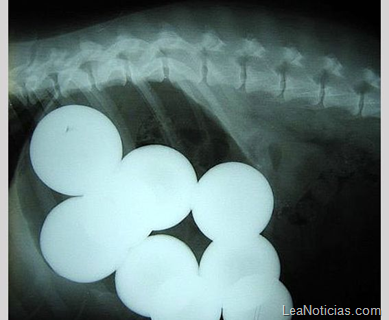

En esta imagen pueden verse unas bolas de billar en el estómago de un perro. La foto la tomó la veterinaria Vanessa Hawksin de Oregón.